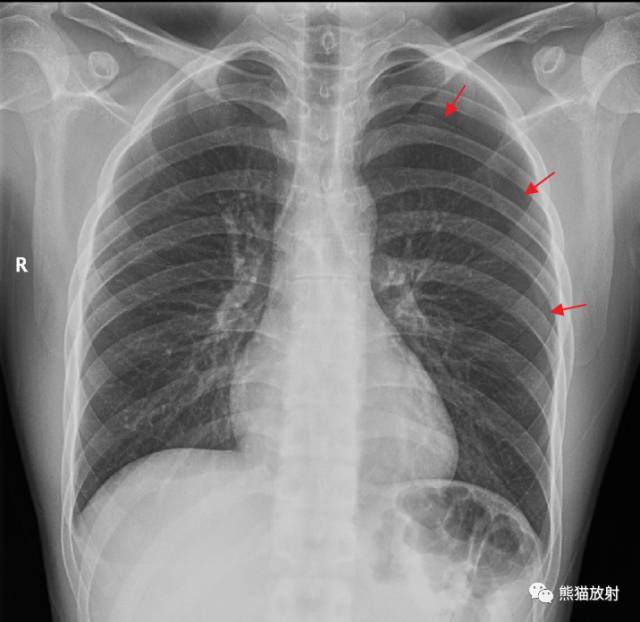

氣胸時如何大體判斷肺被壓迫的程度?氣帶寬度相當(dāng)于患側(cè)胸廓的1/4時,肺被壓縮約35%;氣帶寬為患側(cè)胸廓的1/3時,肺被壓縮約50%;氣帶寬為患側(cè)胸廓的1/2時,肺被壓縮約65%;氣帶寬度占患側(cè)胸廓的2/3時,肺被壓縮約90%??傊?,在判斷肺被壓迫的程度時,只要建立立體的空間概念,不難理解上述估計。左側(cè)氣胸(肺被壓縮約20%):X線正位:左側(cè)胸腔可見移位的胸膜線影,其外側(cè)為條帶狀無紋理區(qū),寬度小于患側(cè)胸廓的1/4。左肺略受壓。胸部CT:左側(cè)胸腔游離氣體,表現(xiàn)為胸頂部及外緣可見弧形無紋理低密度區(qū),左上肺略受壓,未見明顯異常密度。左側(cè)氣胸(肺被壓縮約40%)?↓:左側(cè)胸腔可見移位的胸膜線影,其外側(cè)為條帶狀無紋理區(qū),寬度小于患側(cè)胸廓的1/3。右側(cè)氣胸(肺被壓縮約70%)?↓:氣帶寬度略大于患側(cè)胸廓的1/2,右肺明顯受壓,可見條片狀高密度影。左側(cè)氣胸(肺被壓縮約95%)?↓:左側(cè)胸腔透亮度廣泛增高,其內(nèi)未見紋理走行,左肺明顯受壓縮小,緊貼于左下肺門處,縱隔略向?qū)?cè)移位。原文鏈接:https://mp.weixin.qq.com/s/D4vYIGyYrpncpOAN0lVl7g